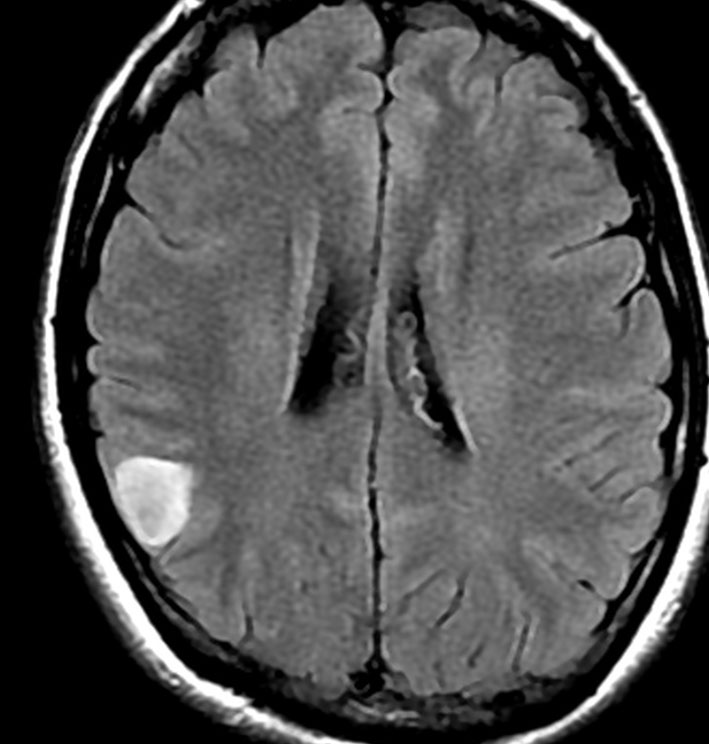

• MRI のT2・FLAIR(フレア)画像で淡く白く見える(高信号)のが特徴です

• 一般的には,びまん性で周囲がはっきりしない脳の中に「にじむような腫瘍」に見えます

• ガドリニウム造影剤で増強されることはほとんどありません

T2-FLAIR mismatch sign (T2とフレアの信号が違うこと)

protoplasmic astrocytomaに特徴的なMRI所見です。T2強調画像(左側)では白く(強い均一な高信号)見えます。でもフレア画像(右側)では白く縁取ったように見えます。びまん性星細胞腫の大きな特徴とされます。内部がとても柔らかいドロドロした腫瘍のこともあります。